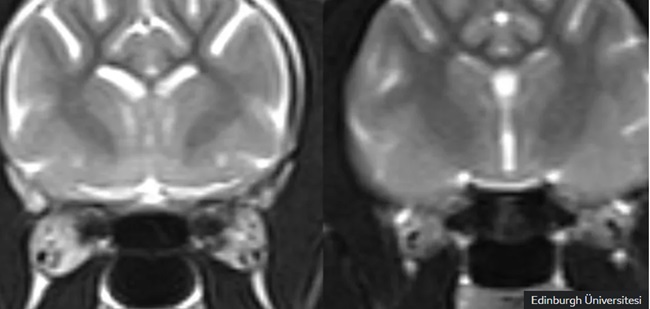

Soldaki MRI görüntüsündeki açık alanlar, sağdaki resimde görülen normal bir kedi beynine kıyasla, bunama hastası yaşayan bir kedide daha fazla beyin dokusu kaybı olduğunu göstermektedir.